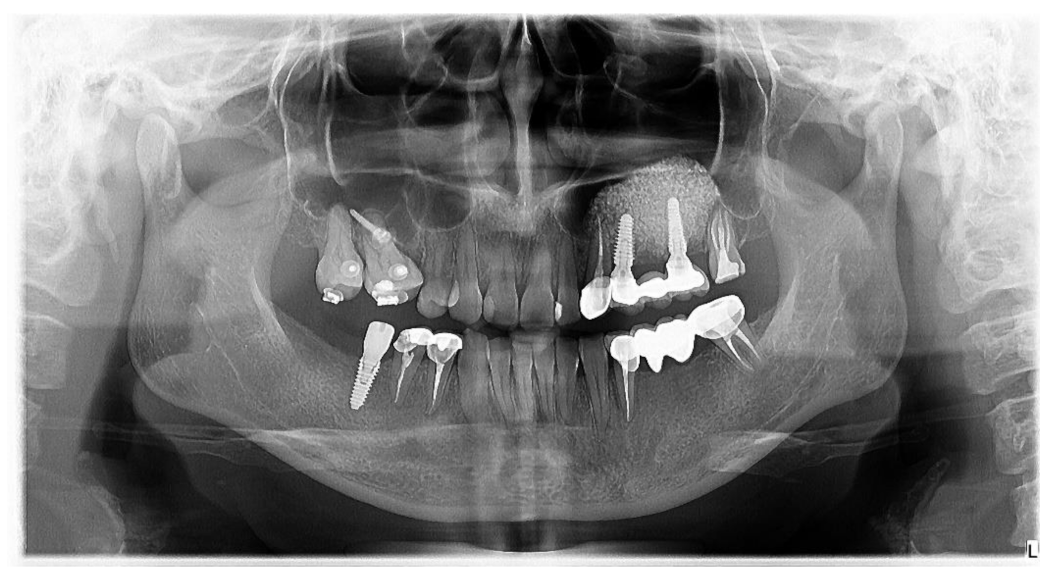

2. Materials and Methods

2.2.1. Pre-Operative CBCT Measurements

2.2.2. Surgical Techniques

2.2.5. Bone Height Evaluation of Newly Regenerated Bone

2.2.6. Evaluation of 1-Year Bone Remodelling